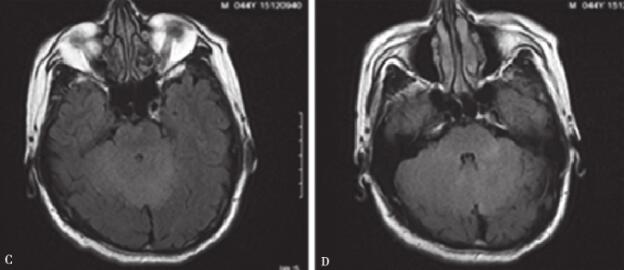

抗炎治疗效果欠佳。行小脑蚓部穿刺活检,病理(图4)为间变性星形细胞瘤(WHOⅢ级)。之后行全脑全脊髓放疗,6-MV X线,分三段进行调强放射治疗,2Gy/次,目前照射11次,患者双下肢活动和头痛症状明显好转。

图4 小脑蚓部病理

A.放大200倍,瘤细胞弥漫分布,密度较高;B.放大400倍,瘤细胞异型性大,见核分裂象;C.放大400倍,瘤细胞呈P53核阳性表达;D.放大400倍,瘤细胞呈Ki-67表达指数较高